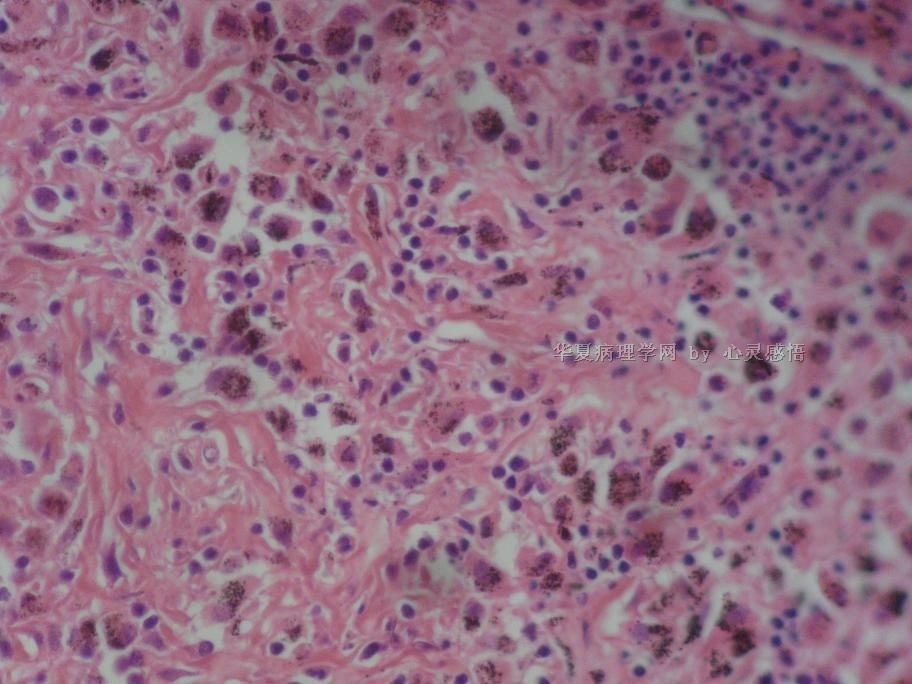

• 食道癌,淋巴结有没有转移,谢谢。图4

图4

1-6图是鳞癌。7-22图片无癌。

淋巴结没有转移

本帖最后由 于 2010-11-17 20:19:00 编辑  图14,19有转移

没有转移。

请教楼主;图片19是淋巴结吗?如果是应该是有癌转移!

没有转移,食道旁的淋巴结和肺旁的淋巴结相似,含有吞噬细胞。